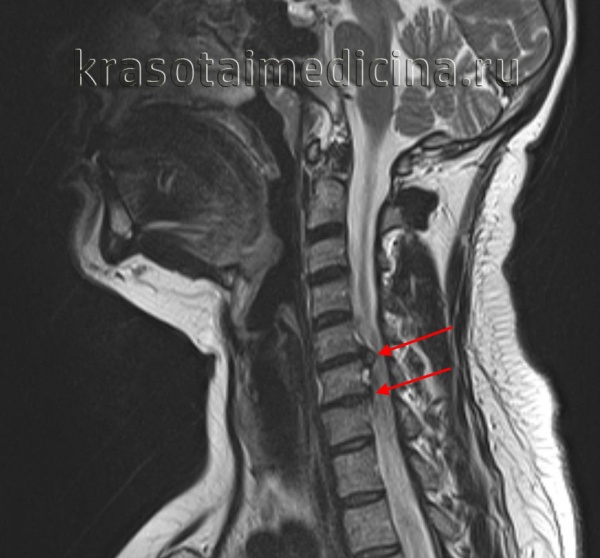

Во время операции были обнаружены два спинных мозга, разделенные костным шипом, покрытым слоем твердой мозговой оболочки (Б). А,Б. Сагиттальная Т1-взвешенная МРТ пациента с плотной утолщенной терминальной нитью (А).

Во время операции нить была идентифицирована, отделена от каудальных нервов, коагулирована и впоследствии удалена (Б).